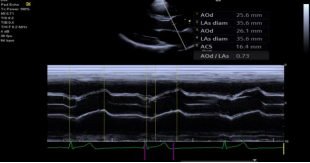

eSie Measure 一键自动测量 :快速自动测量心脏的 2D/M/PW 图像,其良好的一致性、重复性、和准确性,降低了手动测量的误差。可测量的参数包括:

‒ 2D:左房、左室、室间隔、室壁径线 EF、FS等

‒ M:主动脉、左房、左室、室间隔、室壁径线 EF.FS 等

‒ Doppler:四个瓣口的血流峰值流速、时间速度积分、减速时间、跨瓣压差、平均压差、E/A、返流流速、压差等